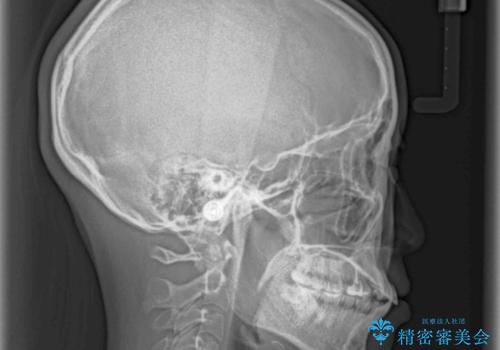

- 八重歯と口元の突出感を気にして来院された患者様です。

歯列が前方に突出しており、上下の正中がズレていたため、左側は上下第一小臼歯を、右側は上下第二小臼歯を抜去し、ワイヤー装置による矯正治療を行うこととしました。